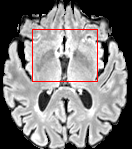

In the MRI CT translation in the Gold Atlas dataset (Fig. 8), major bones and muscles are translated faithfully. Yet, diffusion sampling leads to some inaccuracies in the outline of bones and hallucinations of the textures of inner organs. Conversely, regression sampling faithfully translates bones while still blurring the inner organs and generating artifacts. This indicates that rendering CTs is under-defined by the given MRI guidance alone.

In the quantitative analysis (Tab. 3), we found a slightly increased performance of sampling with over regression sampling in terms of PSNR and accuracy of the downstream task. As performance gains are marginal and the assessment is based on few () test cases, we still assume the performance of diffusion and regression to be similar.

Diffusion sampling YODA results in hallucinated organ shapes and textures that smoothen out and disappear when increasing the in Exp sampling or when using regression sampling. Regression sampling creates some artifacts. Note that, for all methods, the translation quality for inner organs is rather poor, whereas bone and muscle translation is reliable.

When benchmarking on the more heterogeneous and lower-quality BraTS dataset (Tab. 2, left), regression sampling of YODA achieved significantly better images than all competing methods in terms of PSNR, SSIM, and downstream glioma segmentation. Similar results were obtained in the IXI dataset (Tab. 2, right), where YODA significantly outperformed all competing methods in SSIM and PSNR. In the full-brain segmentation conducted from the synthetic images, YODA’s images were significantly better than all competing methods in at least either the Dice score or the HD. In the MRI CT task on the small pelvic dataset, regression and ExpA sampling achieved the highest SSIM, whereas the DB of Choo et al. [31] had the highest PSNR. Both, regression and ExpA sampling YODA also performed competitively in the downstream segmentation task. Note that, for all methods, the translation of inner organs was rather poor and included either texture hallucination (ResViT, I2I-Mamba, diffusion-sampling YODA) or an over-smooth image appearance (Choo et al. [31], SelfRDB, SynDiff, ExpA and regression sampling YODA, Fig. 8).